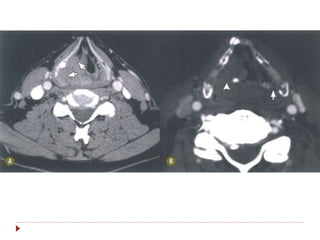

Hipofaringe

 Do osso hioide ao esôfago cervical.

 Três áreas de interesse:

 Seio piriforme (65%).

 Região pós-cricoide

 Parede posterior

 Os linfáticos drenam para cadeia

jugular e cruzam para o lado

contralateral (II, III, V e

retrofaríngeos).

 Sintomas: disfagia, rouquidão,

dispneia.

 Patologia: CEC.

Hipofaringe  Do ossohioide ao esôfago cervical.  Três áreas de interesse:  Seio piriforme (65%).  Região pós-cricoide  Parede posterior  Os linfáticos drenam para cadeia jugular e cruzam para o lado contralateral (II, III, V e retrofaríngeos).  Sintomas: disfagia, rouquidão, dispneia.  Patologia: CEC.